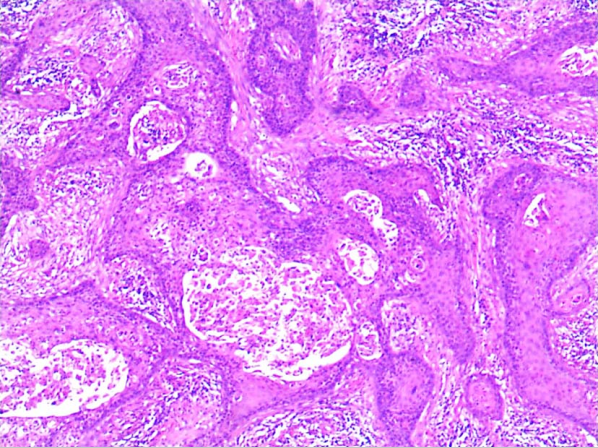

(1)显微镜检

1)微小浸润性鱗状细胞癌:指在HSIL(CIN3)基础上镜检发现小滴状、锯齿状癌细胞团突破基底膜,浸润间质。诊断标准见临床分期。

2)浸润性鳞状细胞癌:指癌灶浸润间质范围超出微小浸润癌,多呈网状或团块状浸润间质。根据癌细胞核的多形性与大小及核分裂程度等可将状细胞癌分为高(Ⅰ级)、中(Ⅱ级)、低分化(Ⅲ级)3种,这种分级法可能提供了肿瘤对化疗和放疗相关的预后信息,但目前更倾向于分为角化型和非角化型。角化型:大致相当于高分化鳞癌,细胞体积大,有明显角化珠形成,可见细胞间桥,细胞异型性较轻,无核分裂或核分裂军见。非角化型:大致相当于中分化和低分化鳞癌。细胞体积大或较小,可有单细胞角化但无角化珠,细胞间桥不明显,细胞异型性常明显,核分裂象多见。除上述最常见的两种亚型外还有以下多种亚型:乳头状鳞状细胞癌、基底细胞样状细胞癌、湿疣样癌、疣状癌、鳞状移形细胞癌和淋巴上皮样瘤样癌。

高分化鳞癌镜下观(40×) 中分化鳞癌镜下观(40×) 低分化鳞癌镜下观(40×)